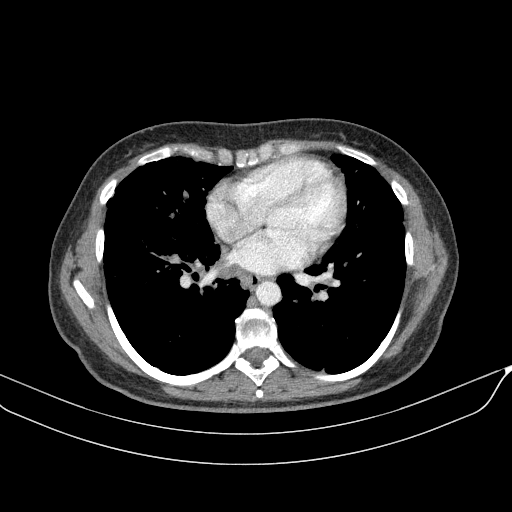

Generated VENOUS CT scan (A→B translation)

No window - Raw intensity values

Lung window (WL -600, WW 1500 β†’ Low βˆ’1350, High +150)

Mediastinum window (WL 40, WW 400 β†’ Low βˆ’160, High +240)

Targeted Slice 70 - Mediastinum Window Analysis (Generated vs Real Venous)

0.759

Mediastinum SSIM

45.2

Mediastinum RMSE

16.1

Mediastinum MAE

Targeted Slice 70 - HU-Space Analysis (Generated vs Real Venous)

0.853

HU SSIM

123.1

HU RMSE

53.0

HU MAE